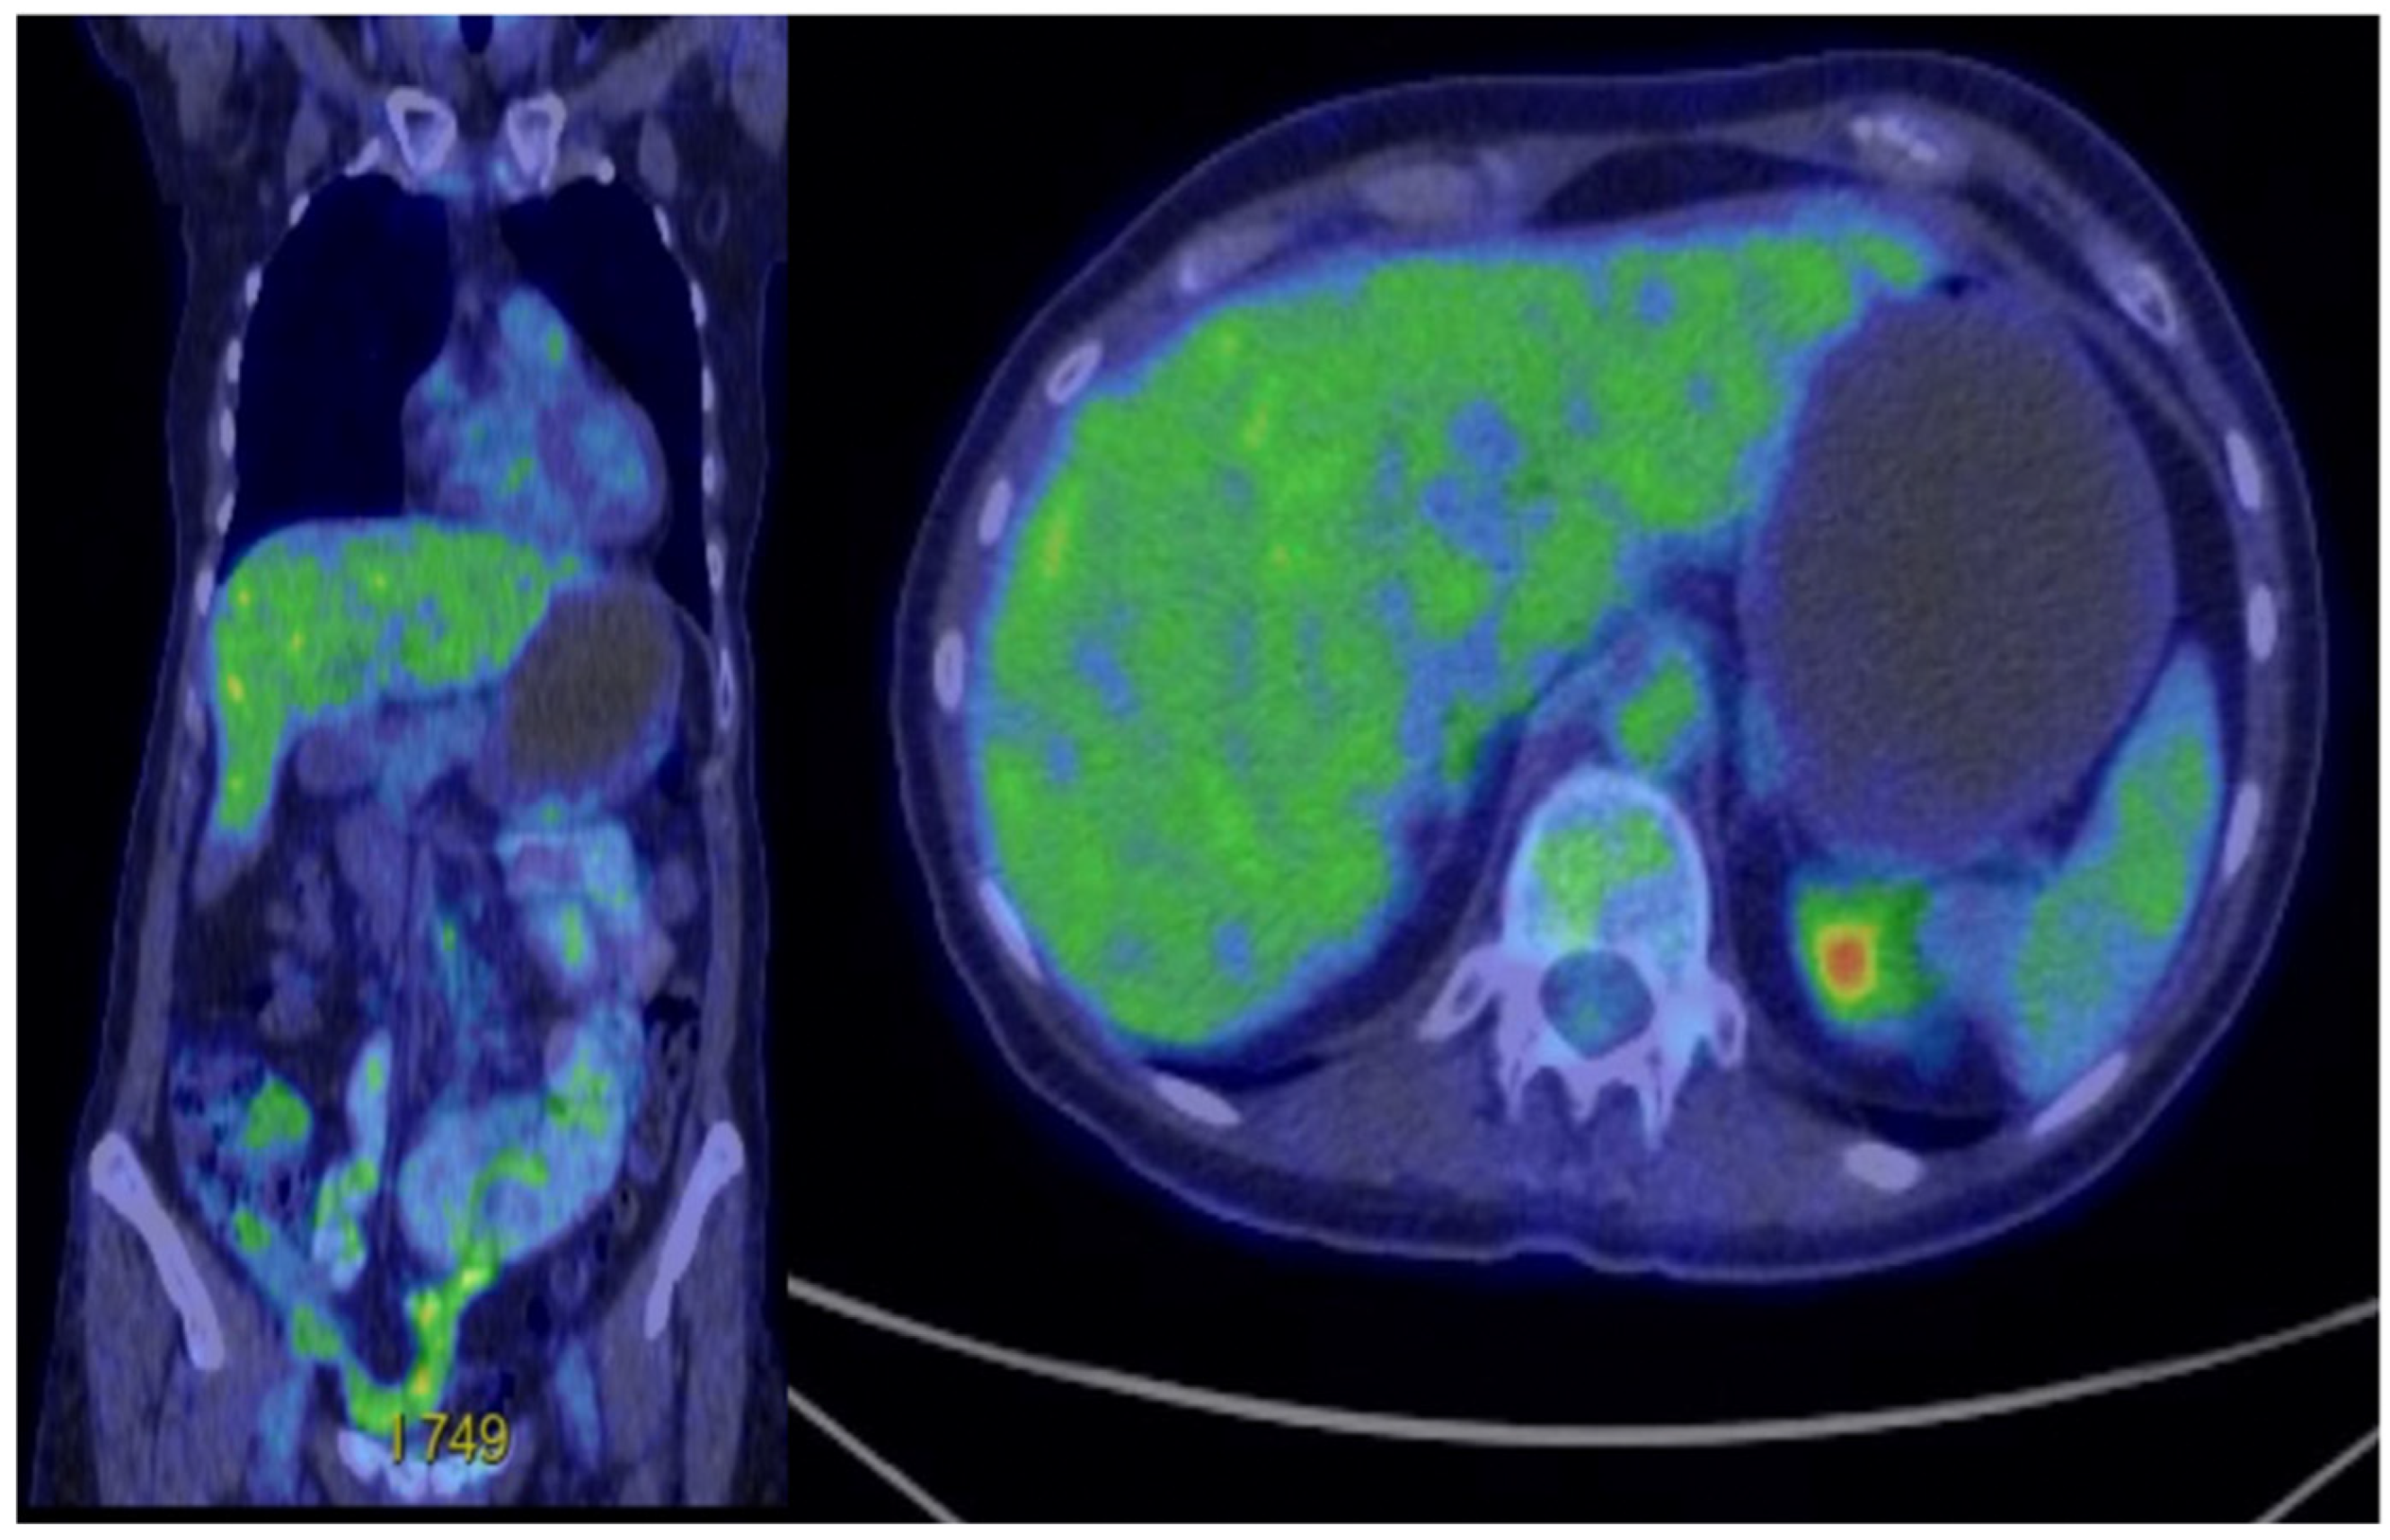

In February 2023, abdominal and pelvic MRI re-evaluation showed no signs of local tumour recurrence at the site of the entero–entero anastomosis. However, it revealed a 2 cm nodular hepatic lesion located at the junction of segments IVa and VIII, along with two additional smaller nodular liver lesions—one at the junction of segments VI and VII, and another within segment VIII. The imaging appearance of these lesions was inconclusive, and further evaluation was recommended, including PET-CT to assess metabolic activity and exclude tumour recurrence, liver MRI for detailed characterization, and a surgical consultation. At follow-up in our clinic, the patient maintained an excellent performance status, with normal laboratory results. Based on these findings, we recommended a liver MRI, PET-CT, and referral for surgical or interventional radiology consultation to consider biopsy and confirm possible disease progression. Subsequent PET-CT confirmed disease relapse, revealing metabolically active perihepatic peritoneal lesions—measuring up to 10 mm near segment IVa/VIII, with additional smaller lesions around segments VIII and VI–VII (with an SUVmax raging between 11–13).

Following surgical consultation, the patient underwent an atypical hepatectomy of segment IVa in May 2023, along with a biopsy of a peritoneal nodule. The procedure was performed for diagnostic purposes and appeared to achieve macroscopic clearance (R1 resection). Final histopathological and immunohistochemical analysis confirmed liver and peritoneal metastases of GNET/CCS, with PD-L1 expression showing a tumour proportion score (TPS) of 15%. Unfortunately, a postoperative MRI revealed two liver metastases showing dimensional progression. A second NGS analysis performed on the liver metastasis did not reveal any additional actionable genetic alterations for treatment selection. The tumour remained microsatellite stable (MSS), with a tumour mutational burden (TMB) of 4 mutations/Mb and confirmed the presence of the EWSR1-CREB1 fusion. PD-L1 expression remained at 15% TPS. The discrepancy of the initial and subsequent molecular tests may reflect tumour evolution over time or technical variability in molecular testing and highlights the dynamic biology of these ultra-rare malignancies. Subsequent PET-CT confirmed progression, with active peritoneal and liver lesions (the hepatic lesion had an SUVmax of 12.4, and the largest peritoneal nodule an SUV max of 11.5). The patient then sought further follow-up and management at another clinical centre, with recommended cytoreductive surgery followed by a combined regimen of immunotherapy and targeted therapy—specifically, nivolumab and cabozantinib. Chemotherapy was considered a secondary option, to be pursued only if the patient was unable to access first-line targeted treatment due to lack of reimbursement by the National Health Insurance Program. Literature data suggest that GNET/CCS cases may respond to various targeted agents, including MET kinase inhibitors (such as crizotinib, cabozantinib, or tivantinib), VEGFR inhibitors (such as pazopanib or sunitinib), and immune checkpoint inhibitors. The therapeutic options we proposed were based on an individualized approach, incorporating the patient’s molecular and tumour-specific characteristics. These included PD-L1 expression of 15% (TPS), presence of the EWSR1-CREB1 fusion, absence of other actionable oncogenic drivers, and a Ki-67 index of 30%. Our decision was guided by case-based evidence from the literature, with the rationale that cabozantinib, a multi-kinase inhibitor, may provide a clinically meaningful response, as well as that co-administration with a PD-1 inhibitor (nivolumab) could counteract T-cell exhaustion, potentially producing a synergistic antitumor effect [19,20]. Due to rapid progression of liver and peritoneal metastases, with minimal response to prior local therapies and a high risk of further disease advancement, achieving a rapid therapeutic response was deemed essential.

Figure 2. Postoperative PET-CT-no residual disease.